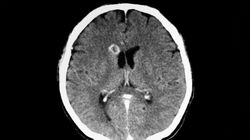

ciąg ze strony 1 FILAR,hipointensywne w obrazach Tl-zależnych odpowiadające plakom demielinizacyjnym.Część zmian wykazuje cechy rozpadu (jama malacyjna o sygnale zbliżonym do sygnału płynu mózgowo-rdzeniowego).Pojedyncze zmiany,głównie w istocie białej półkul mózgu,ulegają brzeżnemu wzmocnieniu po podaniu dożylnym paramagnetyku co przemawia za ich aktywnością.

MĘŻCZYZNA, 50 LAT ponad rok temu